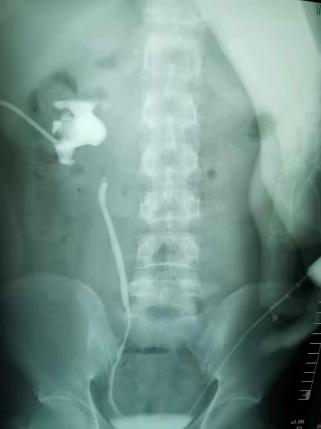

顺行+逆行静脉肾盂造影显示输尿管上段不显影

徐冉副主任介绍,该患者术前检查可见患者输尿管上段很长一段不显影说明狭窄范围很广,加之患者多次手术更加加大了此次手术的难度。